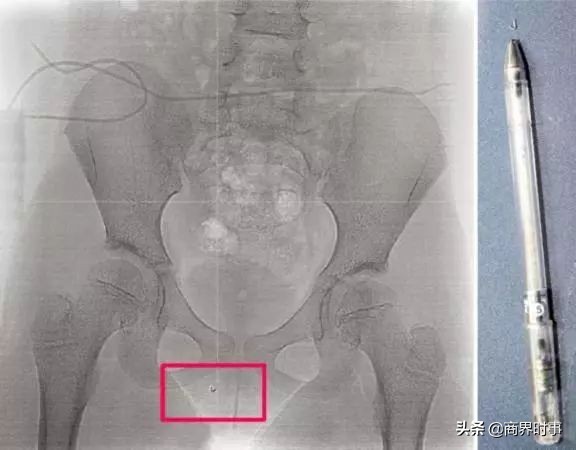

喊到“八月”的时候,一男孩趁着同桌女生站起来,在其凳子上90度垂直放置了一根油性笔,笔尖朝上。

女孩毫无防备坐下的那一瞬间,笔尖戳破她的右侧大腿,直插入会阴部并滞留体内。

事发后,男孩家长没有第一时间出面赔偿道歉,反而替儿子请了3天假,说是要安抚孩子的情绪,还以“还是个孩子”为由,将一半责任推给学校。